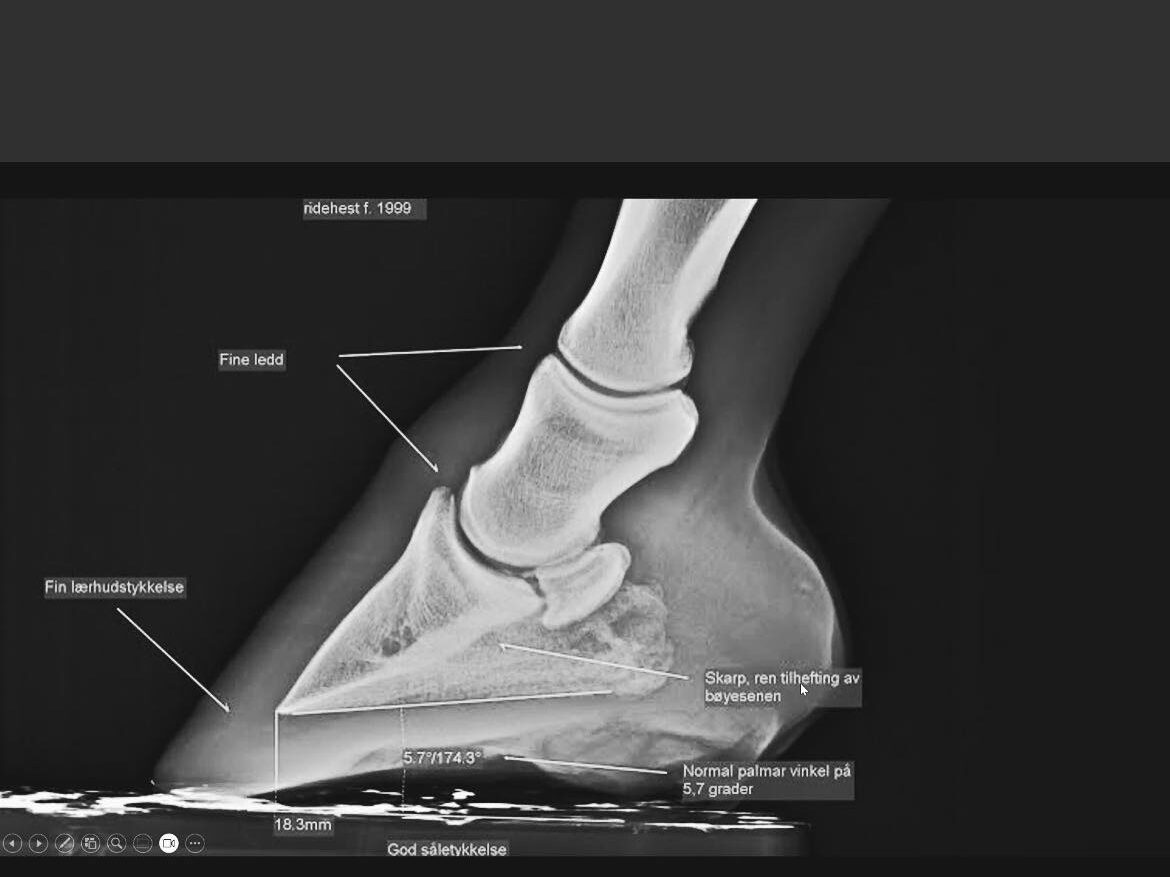

Hur kan vi förstå hästens hovar och rörelse bättre genom röntgen?

I den här clinicen får du en unik möjlighet att följa med när hovvårdare och veterinär samarbetar om verkning med hjälp av röntgenbilder. Vi tittar på hur hovens inre strukturer ser ut, hur olika verkningar och skydd påverkar, och vad man kan lära sig av att jämföra det man ser på utsidan med det som finns på insidan.

Vi kommer även röntga hovar med några olika skor och bootsmodeller, för att se och prata om hur de påverkar hovar och rörelse.

Upplägget består av både teori och praktik. Vi kommer att röntga hovar på plats innan och efter verkning, diskutera resultaten i grupp och resonera kring olika lösningar. Fokus ligger på att bygga förståelse och skapa dialog mellan yrkesgrupper – alltid med hästens bästa i centrum.